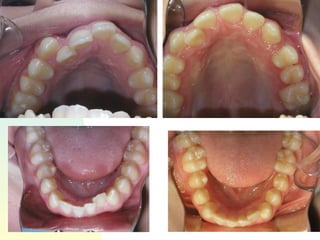

Patient   : J.R, male DOB :7/20/91, start of tx age: 12yr 9mo Ethnicity : American-born Hispanic, English-speaking Health Hx :  WNL, unremarkable Dental Hx :TMJ=WNL, OH=B+, midline=on, molar R&L= Cl 1, OB=40%, OJ= 1mm, dental anterior cross-bite, crowded max & mand anteriors, caries #15-O, #18-O,B, perio=WNL Psychosocial : Parents are separated,  1 younger sister,1 older sister.  Mom had ortho tx --- 4 premolars & 4-3rd molars extracted, “My braces hurt and I don’t want a lot of teeth pulled on my son”. Chief complaint :  “I don’t like the way my teeth stick out in front.”

31.6 35.7 44.4 42.3 29.6 Schwarz analysis SI=31.6, Max 4-4’s ideal = 39.6   actual 35.7 difference= -3.9 Max 6-6’s ideal= 47.6 actual 44.2 difference= -3.2  total -22.4 Man 4-4’s ideal= 39.6 actual 29.6 difference= -10 Man6-6’s ideal= 47.6 actual 42.3 difference= -5.3

31.6 35.7 44.442.3 29.6 Schwarz analysis SI=31.6, Max 4-4’s ideal = 39.6 actual 35.7 difference= -3.9 Max 6-6’s ideal= 47.6 actual 44.2 difference= -3.2 total -22.4 Man 4-4’s ideal= 39.6 actual 29.6 difference= -10 Man6-6’s ideal= 47.6 actual 42.3 difference= -5.3